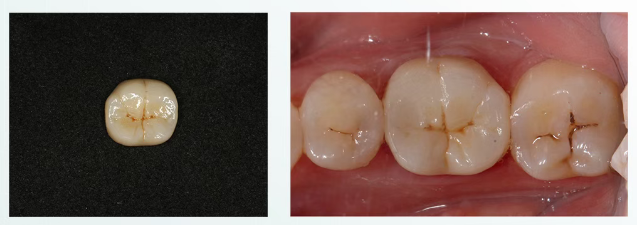

第五次就诊

去除暂冠,清洁基牙,隔湿,玻璃离子粘接。

4个月复查

戴牙四月复查,可见修复体及牙周情况良好,

正常行使功能,日常使用无异常。